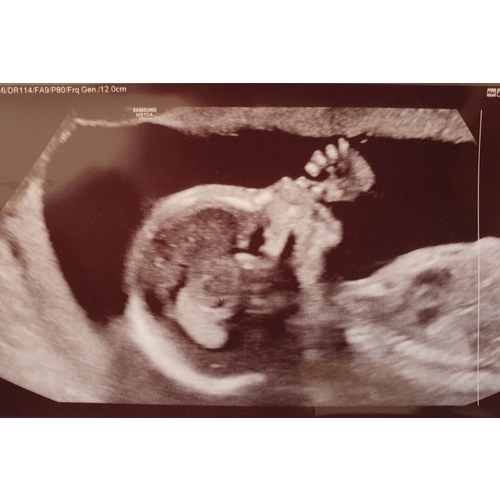

Vanmorgen ook de 20 weken echo gehad en bij ons was gelukkig ook alles goed. Was behoorlijk nerveus maar de kleine meid groeit goed en het zag er allemaal goed uit gelukkig🥰

Fijn hè om te weten dat alles goed is👍🏻 wij hebben de 20weken echo 24feb gehad en ook bij ons gelukkig alles goed. Die was onze eerste echo, twee voetjes naast elkaar 💙💙💙

26 maart een perfecte 20 weken echo gehad 🥰 ze zat zelfs boven het gemiddelde moest tussen de 350 gram en 400 gram zijn en ze was 409🥰 en ze had hele grootte voetjes bijna 36 mm 😂 al met al ik kan niet wachten om haar 23 april weer te zien!

Ik heb de echo een tijd geleden ingepland met 21 weken, zodat mijn man mee kon. Vandaag de afspraak vervroegd, want partner mag toch niet meer mee. Nu mag ik zaterdag 4 april komen, ben zo benieuwd nu ik jullie mooie foto's zie! Ik voel de baby best vaak sinds 1,5 week, dat wordt nog wat op de echo 😂

Ik heb morgen eind vd middag de 20 weken echo en mijn vriend blijft in de auto met de ipad om te videobellen. Ben mega nerveus😔 hoop zo dat alles goed is met ons kleine meisje.. Ik hou me maar vast aan het feit dat de nipt en 15 weken geslachtsbepalings echo super goed waren en goed op groei en ze al best wat konden zien aan vloeistoffen in de blaas en maag en hersenhelftjes goed verdeeld. Maar pff wat mis ik de controle bij de verloskundige om even het hartje te horen. Ook al voel ik haar elke avond kriebelen.🙈 Ben blij als morgen voorbij is en ik een beetje zekerheid heb hopelijk! 🙏

Jullie hebben de lengte en gewicht te horen gekregen van jullie kindje? Ik niet, sowieso was het super gehaast (door Corona houden ze alles zo kort mogelijk, bizar genoeg)